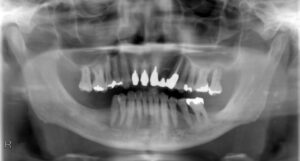

下顎臼歯2本欠損症例

BEFORE AFTER 63歳男性/下顎臼歯2本欠損/インプラント埋込手術 【治療内容】 下顎の大臼歯が左下第一大臼歯…